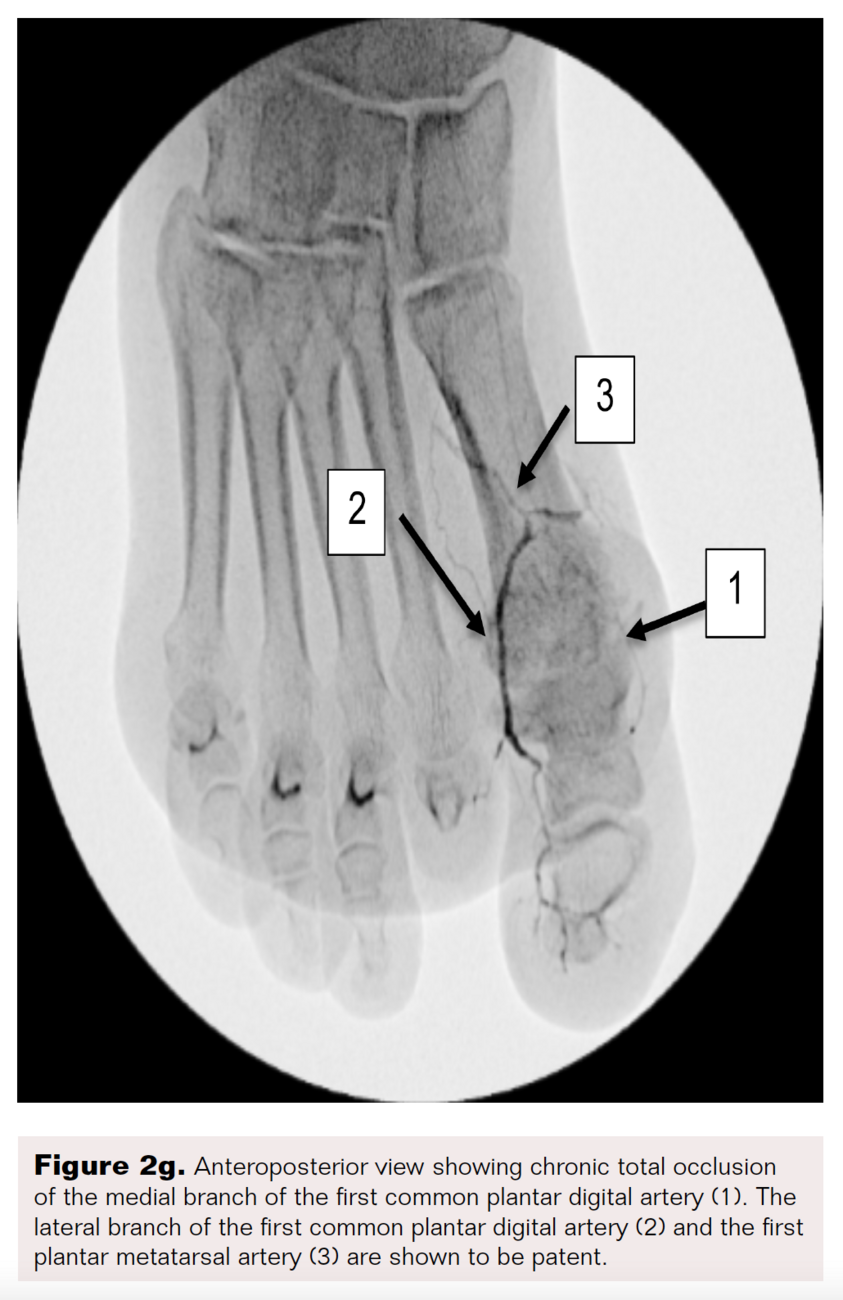

However, the entirety of the medial plantar artery (MPA) distribution was chronically occluded shortly after take-off (Figure 2E and Figure 2F). Super-selective angiography revealed chronic total occlusion of the medial branch of the first common plantar digital artery arising from the first plantar metatarsal artery (Figure 2G). Angiography also revealed an occluded accessory branch arising medially from the superficial branch of the MPA.

The anatomy of the arteries supplying the hallux is complex, with variants being common. In this patient, an atypical accessory branch arising from the superficial branch of the MPA was present. While the arterial anatomy of hallux-supplying arteries and its corresponding variants are not readily discussed in recent literature, certain textbooks do depict an accessory branch arising from the superficial branch of the MPA.2 The accessory branch of this patient, in particular, communicated with the first dorsal metatarsal artery arising from the DPA (Figure 2F) and the superficial branch of the MPA communicated with the medial branch of the first common plantar digital artery arising from the LPA (Figure 4C). In general, using the angiosome concept, the blood supply to the hallux consists of 3 main avenues: (1) the first dorsal metatarsal branch arising from the DPA; (2) the plantar digital arteries arising from the first plantar metatarsal artery, which is a branch of the LPA; and (3) the superficial branch of the MPA.3,4 The latter 2 sources of blood supply were absent in this case.